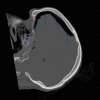

Tension pneumocephalus (TP) is the intracranial equivalent of tension pneumothorax. It is an unusual but life-threatening neurosurgical emergency, which has been described following head trauma, epidural injections or complicating neurological, spinal, craniofacial or sinus surgery. Unfortunately, the signs and symptoms of TP are non-specific and the diagnosis must be made by prompt recognition of the classic imaging signs of TP, allowing lifesaving emergency decompression. We present a trauma patient demonstrating the "Mount Fuji" sign on an unenhanced CT scan of the brain, which is reportedly specific for TP.